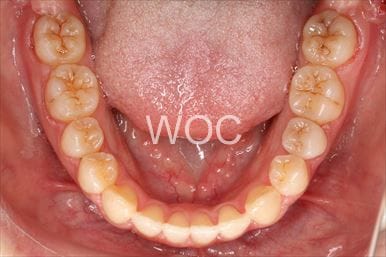

治療前2

治療前3

治療前4

治療前5

- 年齢:20歳女性

- 主訴:出っ歯が気になる

- 基本矯正料金:120万円

- 治療期間:1年7ヶ月

- 抜歯部位:上顎両側第一小臼歯